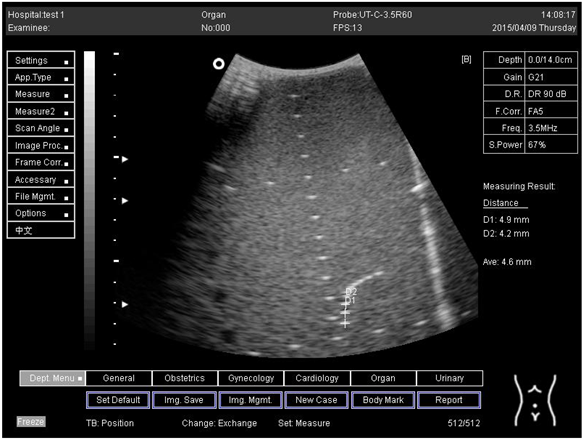

Depth (cm)DiagramDistance (mm)

14.0Axial resolution

Biomimetics 07 00130 i023

D1 = 4.9

D2 = 4.2